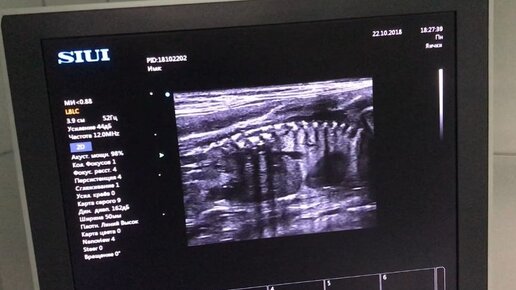

Сегодня мы сделали плановое УЗИ двум нашим кошкам: Саманте и Барселоне. У Саманты срок ровно 1 месяц, мы насчитали 6 плодов. Размер плодных яиц 3, 5 на 2 см . Уже отчетливо видно сердцебиение, дифференциация тела на голову и туловище. Мы очень ждем этих малышей, ведь Саманта несколько раз пропустовала, и мы переживали за нее, поэтому так рады наступившей беременности! Второе УЗИ мы делали Барселоне, которой рожать довольно скоро, мы так и не смогли посчитать малышей, потому что на этом сроке уже легко ошибиться, посчитав дважды один и тот же плод...